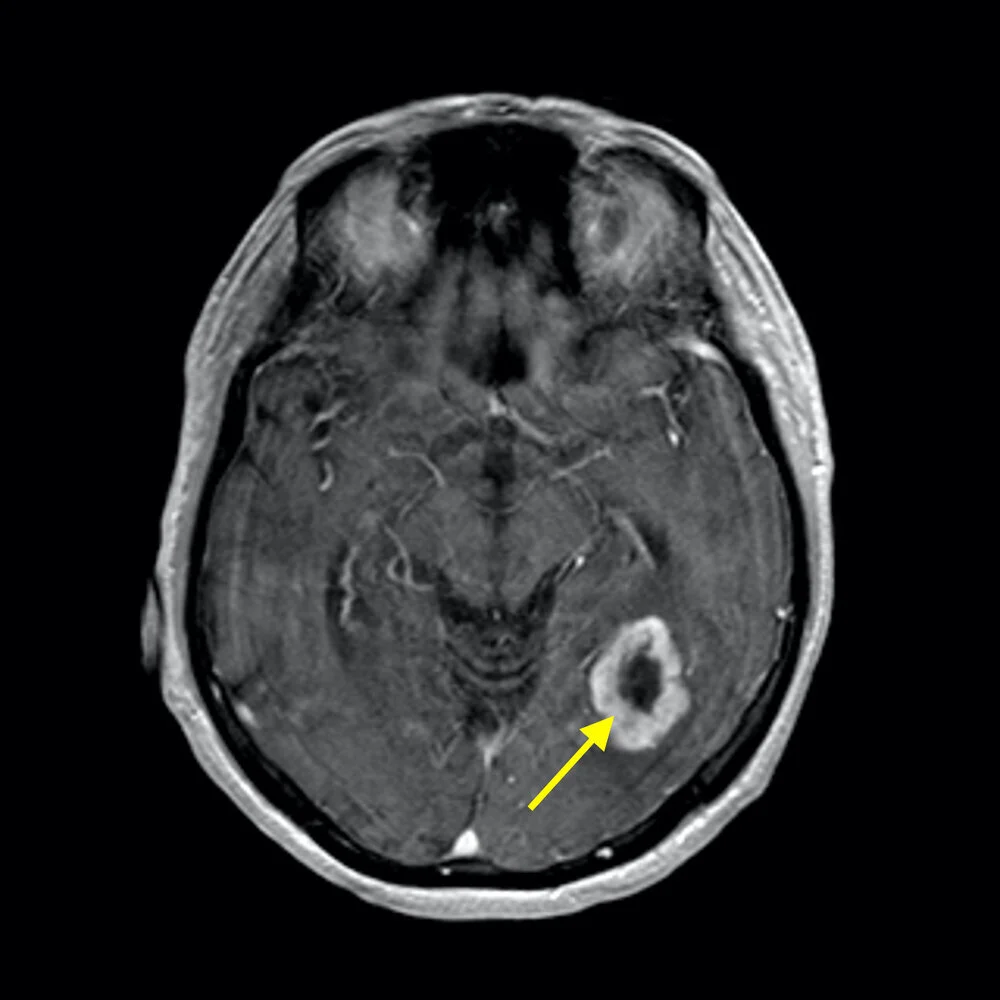

MRI scan from a patient with left temporal-occipital high grade glioma (glioblastoma or GBM)